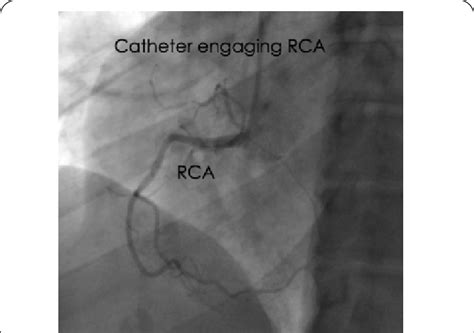

Left heart catheterization. Mild luminal irregularities of the left